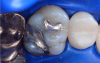

Fig 3. Occlusal view of the tooth before the restoration.

Figure 3

In this case, a female patient presented with an asymptomatic tooth that had an incomplete fracture on the distal palatal cusp and potentially the distal buccal cusp.1 The patient was highly motivated to avoid extensive dentistry and had "dead jaw syndrome" from a history of using bisphosphonate medication (Figure 1 through Figure 4). The solution was to perform a composite overlay on the tooth.

To begin this Class II restoration, the first step was to completely remove the old restoration and properly prepare the overlay. In this case, there was an incomplete fracture of the distal buccal cusp and underneath the distal palatal cusp. Although the tooth structure was cracked, it was not desirable to amputate the fracture because the tooth structure itself was good, so the plan was to treat it as buildup material.1 Building a good contact is one of the most crucial steps to ensuring the final restoration is successful.